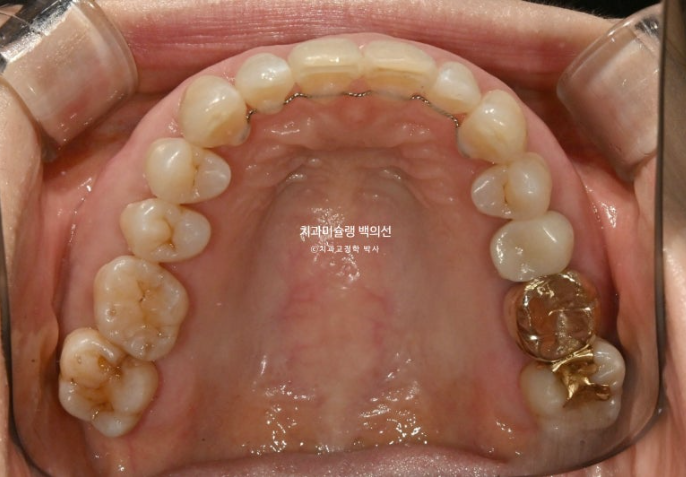

이제 전 후 비교 보겠습니다.

24.09~25.09

파란 화살표 치아가 치주염이 심해 발치한 치아입니다.

1년간의 교정치료 기간 동안 잇몸뼈는 잘 유지가 되었고 치근평행도는 양호합니다.

개인적으로 안 보이는 부분까지 완벽을 기하기 위해서 치근평행도에 집착하는 편입니다만 아래 앞니 뿌리가 완벽히 평행하지 못한 부분이 조금 아쉽습니다.

파란화살표가 발치한 치아 자리이고 이미 심한 치주염으로 골손실이 심해 인접치아 뿌리가 해당 부위로 충분히 이동해주지 못하기 때문입니다.

뼈가 튼튼해야 그쪽으로 치아이동이 잘 됩니다. 반대로 뼈가 없는 부위로 치아가 이동하진 못합니다.